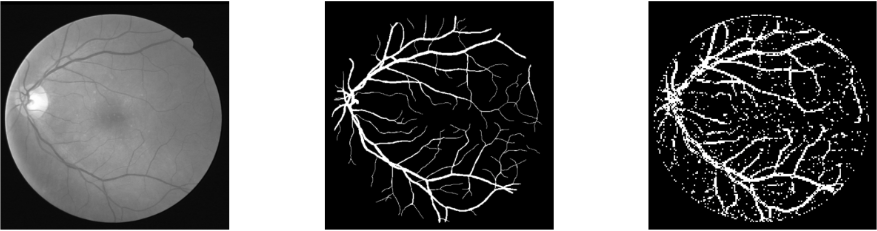

Wyniki i efekty

- Dokładność (accuracy): 89% – całkiem nieźle jak na prosty model bez głębokiego uczenia!

- Czułość (recall): 85% – dobrze wykrywał naczynia krwionośne, ale czasami mylił je z cienkimi liniami tła.

- Precyzja (precision): 91% – model dość skutecznie unikał fałszywych alarmów (błędnego oznaczania tła jako naczyń).

Wiem, że efekt na pierwszy rzut oka nie powala i można się zastanawiać, jakim cudem udało się uzyskać tak dobre “cyferki” (czyli dokładność). Ale tu właśnie tkwi mały szkopuł, czyli narzucone wymaganie.

Chciałbym zaznaczyć, że do uczenia modelu wykorzystałem wycinki o rozmiarze 3x3 pikseli, ponieważ na tak małych fragmentach model łatwiej wykrywa lokalne wzorce charakterystyczne dla naczyń krwionośnych.

Całkowity rozmiar obrazu to 512x512 pikseli, więc jeśli klasyfikator stwierdził, że dany wycinek to naczynie krwionośne, to te 9 pikseli (3x3) w rezultacie zostało w całości wypełnione na biało.

- Dokładność (accuracy): 92% – co jest wyraźną poprawą w porównaniu do KNN.

- Czułość (recall): 90% – model świetnie radził sobie z rozpoznawaniem naczyń nawet w trudniejszych przypadkach.

- Precyzja (precision): 94% – minimalna liczba fałszywych alarmów i bardzo precyzyjne wykrywanie naczyń.